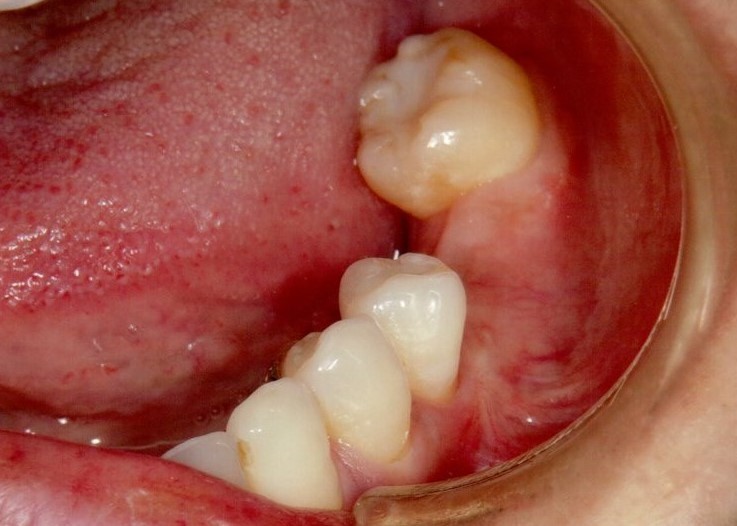

奥歯インプラント(スクリュー固定)

(伊東市 女性)

治療の流れ

むし歯で歯を失ってしまいました。

インプラントを埋入し、最終的な被せ物を装着しました。(ネジ穴をふさぐ前)

ネジ穴をふさぐとこの様な状態になります。